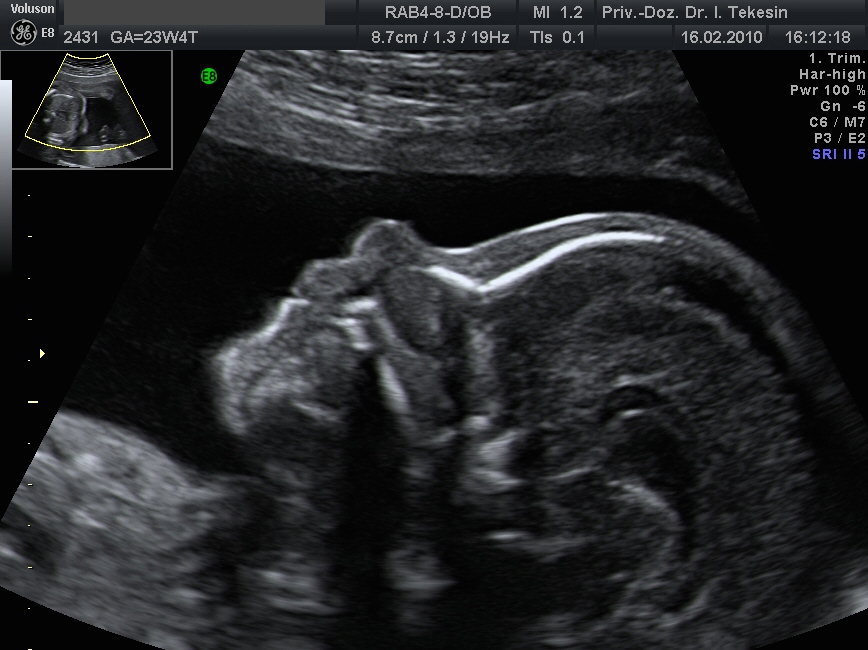

Die Ultraschalluntersuchung ist ein bildgebendes Verfahren, das nach heutigem Kenntnisstand selbst bei wiederholter Anwendung keine Schäden bei Mutter und Kind verursacht. Eine Ultraschallfeindiagnostik können wir Ihnen optimal zwischen der 20. und 22. SSW anbieten.

Entscheidende Rolle bei dieser Untersuchung spielt die Lage des Kindes und die Stärke der mütterlichen Bauchdecken. Dabei betrachten wir alle darstellbaren Organe und Merkmale des Ungeborenen: das altersentsprechende kindliche Wachstum, die Fruchtwassermenge, das Aussehen und die Funktion aller sichtbaren Organe und die Lage und das Aussehen der Plazenta.

Profil in der 21. Woche

Profil in der 25 Woche